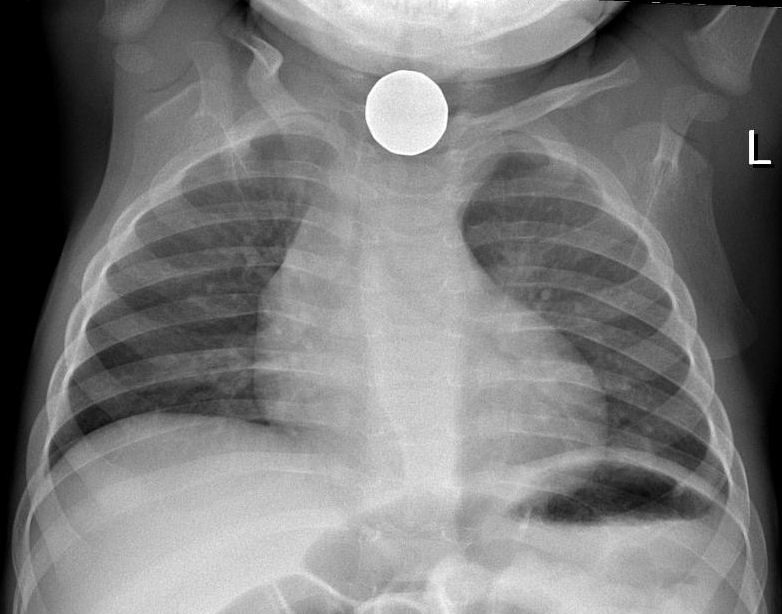

В результате проведенной рентгендиагностики инородных тел в пищеводе были получены следующие результаты:

- В 75% из случаев удалось точно определить наличие инородного тела в пищеводе.

- В 25% случаев были выявлены инородные тела, которые не были обнаружены другими методами диагностики.

- Определение размеров инородных тел позволило определить возможность их самостоятельного прохождения или необходимость их удаления.

- Рентгендиагностика позволяет оценить степень повреждения пищевода при наличии инородного тела и определить появление осложнений.

- Удаление инородных тел после рентгендиагностики позволило избежать различных осложнений и оперативных вмешательств.

Таким образом, результаты рентгендиагностики свидетельствуют о высокой эффективности этого метода при обнаружении инородных тел в пищеводе. Раннее и точное выявление таких случаев позволяет предпринять необходимые меры для их удаления или предотвратить возможные осложнения.